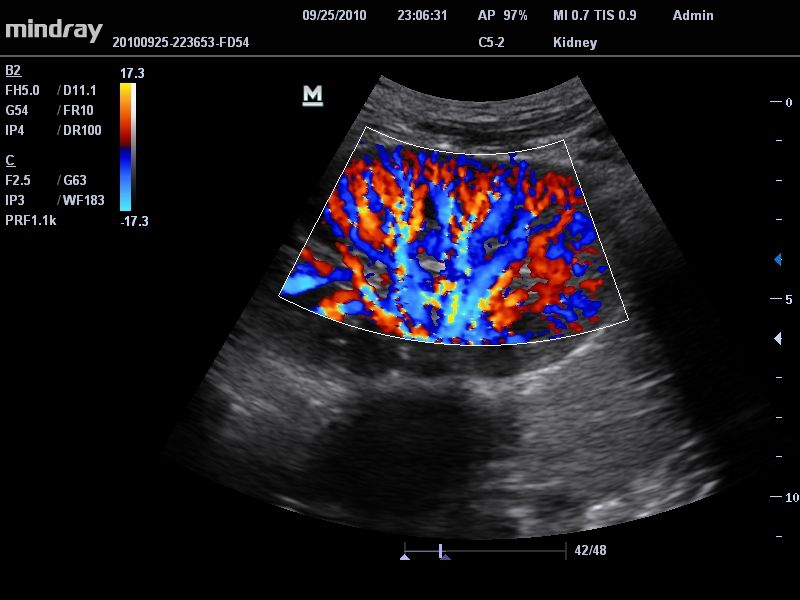

Энергетический допплер:

Да

Цветовой допплер:

• Режимы сканирования: B/M/CFM/PDI/Направленный PDI/PW, HPRF, Тканевая гармоника, М- и цветной М-режим.